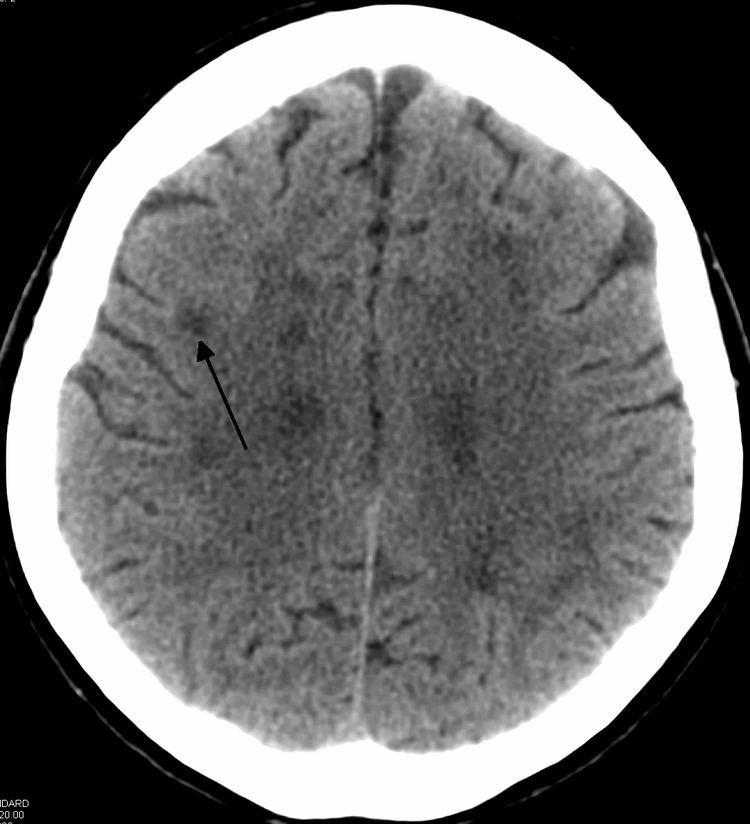

Neuroimaging

Standard MRI scans have been performed on 1.5 Tesla scanners with 5 mm thickness and 5 mm spacing to screen for white matter lesions in identified families. If signal intensities of the MRI scans are higher in white matter regions than in grey matter regions, the patient is considered to be at risk for HDLS, although a number of other disorders can also produce white matter changes and the findings are not diagnostic without genetic testing or pathologic confirmation.